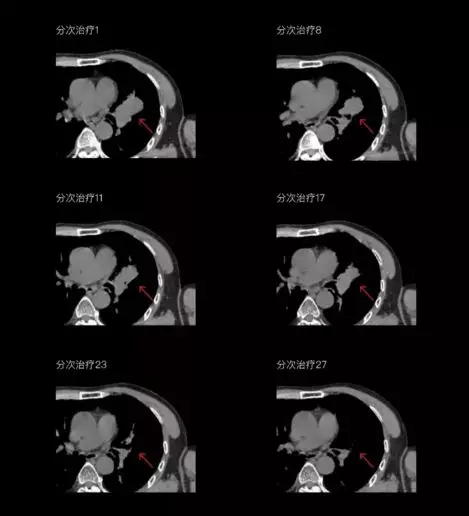

聯(lián)影CT-linac全程監(jiān)測(cè)治療過(guò)程病灶的變化,及時(shí)調(diào)整和優(yōu)化治療方案

一體化CT-linac讓自適應(yīng)放療ART概念變?yōu)楝F(xiàn)實(shí)?;颊呷煶虪顟B(tài)監(jiān)控,適時(shí)在線調(diào)整治療計(jì)劃,精準(zhǔn)控制治療劑量,為患者動(dòng)態(tài)定制個(gè)體化治療方案。uAI賦能智能勾畫(huà)和自動(dòng)計(jì)劃,秒級(jí)勾勒靶區(qū)和危及器官,大幅縮短自適應(yīng)放療時(shí)間。